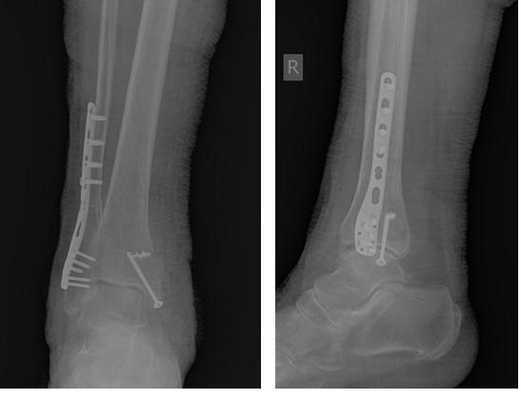

В день обращения пациентка послоностью обследована, проведено оперативное лечение, открытая репозиция, остеосинтез перелома нижней трети малоберцовой кости пластиной, внутренней лодыжки винтом, внутренняя лодыжка дополнительно фиксирована анкерным фиксатором.

На контрольных рентгенограммах после операции положение отломков, металлофиксаторов правильное, подвывих таранной кости устранён.

Пациентка выписана на 2 сутки после операции на амбулаторное долечивание.